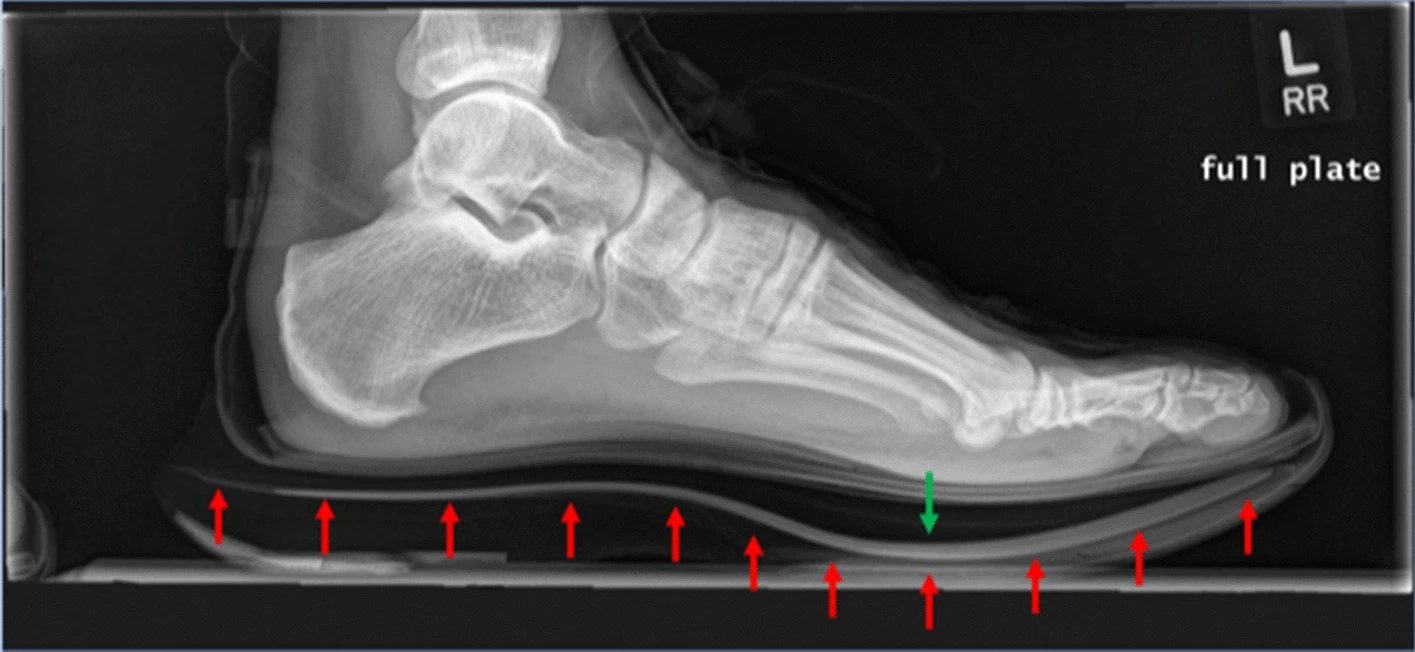

Waarom train ik er dan niet altijd op, en waarom raden mensen vaak af om er veel op te trainen? Het antwoord is eigenlijk heel simpel, er is op dit moment nog niet bekend wat het effect is van de super schoen op lange termijn. Kan het type foam dat ze gebruiken voor de middenzool een impact hebben op je spieren en pezen? Kan de carbonplaat een impact hebben op je blessure gevoeligheid? Het is allemaal mogelijk.

Er zijn wel wat onderzoeken gedaan, en er is wat anekdotisch bewijs met betrekking tot zowel de voor- als de nadelen. Een van de onderzoeken (hier besproken door Doctors Of Running) wees bijvoorbeeld uit dat mensen die op super schoenen liepen in plaats van “racing flats” minder spierpijn ervaarde. (DUH!) Als het aan komt op anekdotisch bewijs, dan hoor je hele tegenstrijdige dingen. De een zegt dat er vaker stress fracturen voorkomen bij mensen die op super schoenen trainen (daar is ook beperkt onderzoek naar gedaan overigens), de ander zegt dat het gebruik van super schoenen juist er voor zorgt dat men sneller hersteld door dat je efficiënter bent (ook daar is onderzoek naar gedaan), en de algehele belasting lager is daar door. Dat klinkt mij nogal tegenstrijdig.

Wat wel duidelijk is is dat het gebruik van een super schoen er voor zorgt dat er een andere belasting is. Die andere belasting kan, zoals het er nu naar uitziet, dus zowel positief als negatief uitvallen. Mijn advies is dus, en welke waarde je hier aan hecht is aan jou, om een degelijke schoen rotatie te hebben en meer in hardloopschoenen zonder carbonplaat te lopen dan schoenen met carbonplaat. (Liefste dus twee verschillende soorten schoenen minimaal.) Heb je een langzame training, gebruik dan geen super schoen, gebruik deze daar waar je er voordeel van kan hebben, zoals een interval training bijvoorbeeld of bij een training met langere blokken op je race tempo, wat dat dan ook moge zijn.